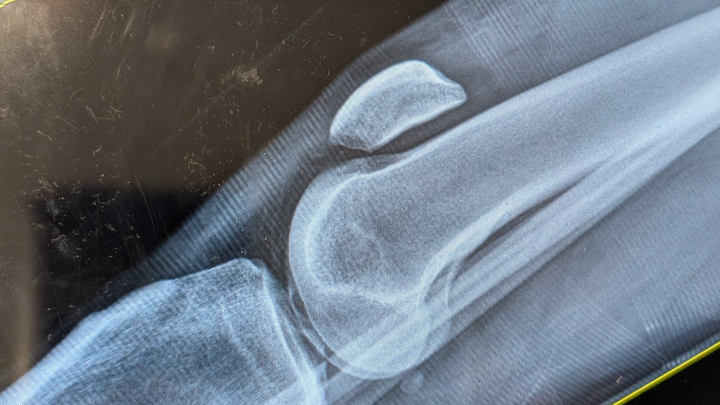

I took a bad fall off a ladder doing some home improvements at my house. I completely tore my patellar tendon, leaving my kneecap floating at thigh level.

The expected recovery time is 4-6 months after surgery, which I am in the process of scheduling.